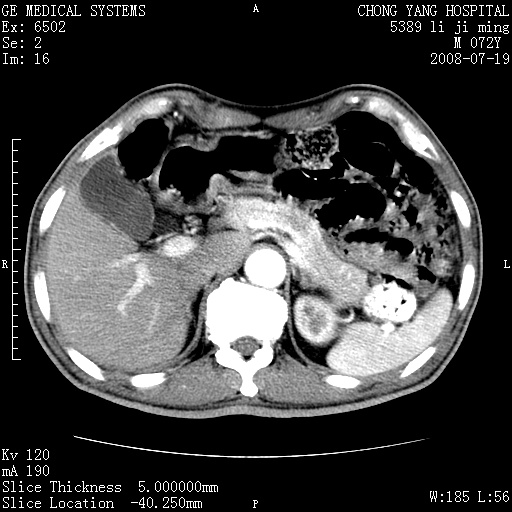

以下是引用zjzjr在2008-7-19 20:57:00的发言:[br]胰头增大,边缘模糊,周围可见渗出影,右侧肾前筋膜增厚.支持胰腺炎.

以下是引用yangyudong333在2008-7-20 6:56:00的发言:[br]胰腺增大尤以胰头明显,边缘模糊,周围可见渗出影,右侧肾前筋膜增厚,肠管於涨.支持胰腺炎

以下是引用不学无术在2008-7-19 23:15:00的发言:[br]胰腺增大尤以胰头明显,边缘模糊,周围可见渗出影,右侧肾前筋膜增厚,肠管於涨.支持胰腺炎